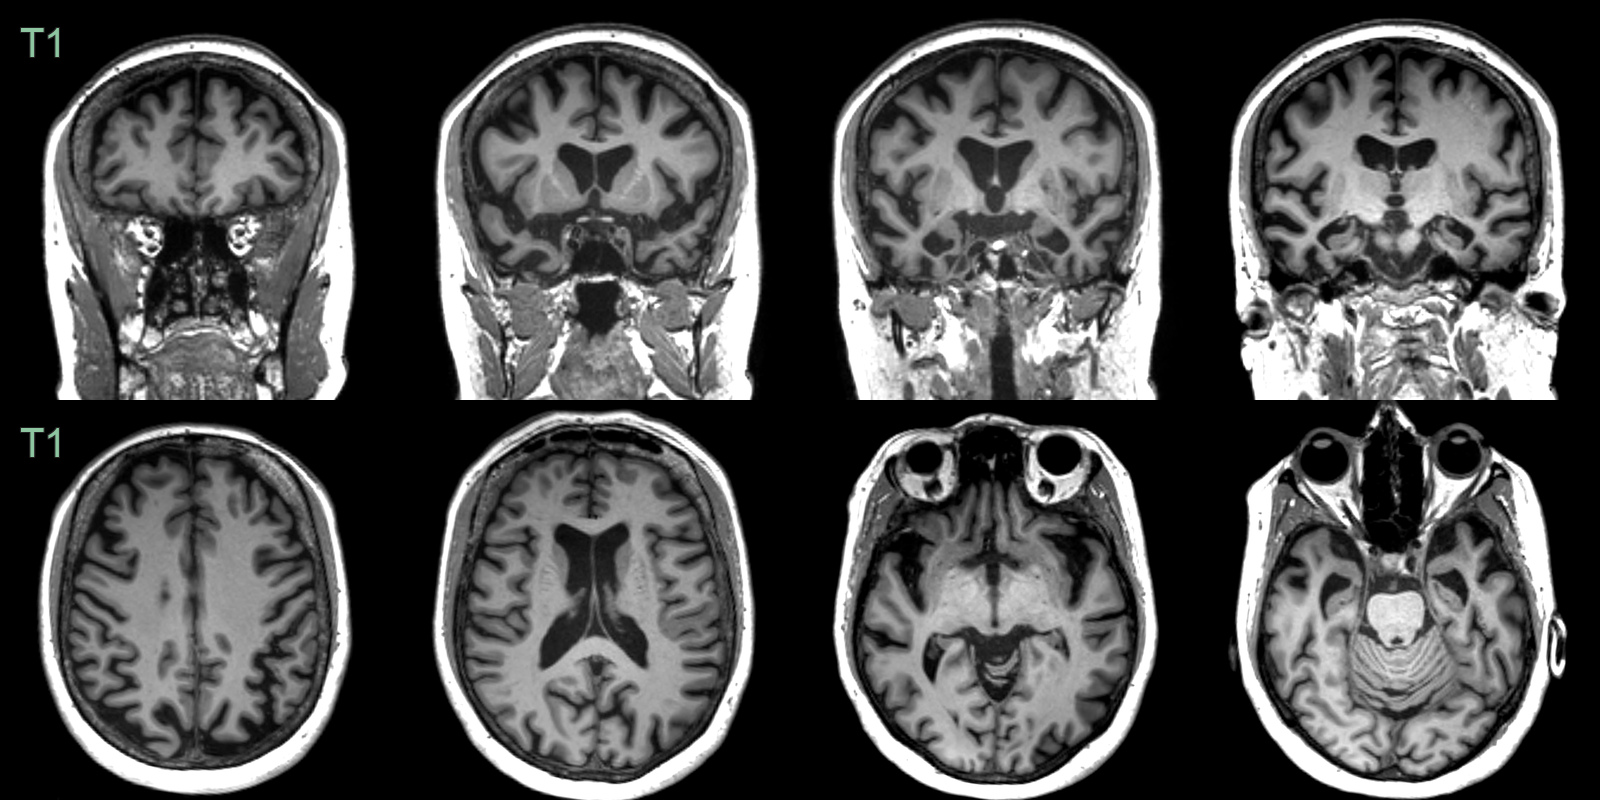

- A 60-year-old patient presented with disinhibition and impaired naming and verbal memory.

- MRI showed pronounced anterior temporal, milder left parietal, and no frontal lobe atrophy. There was particularly pronounced atrophy of the amygdalae.

- CSF amyloid markers were normal, making Alzheimer's disease unlikely. Genetic testing revealed a MAPT mutuation as the cause of frontotemporal dementia.